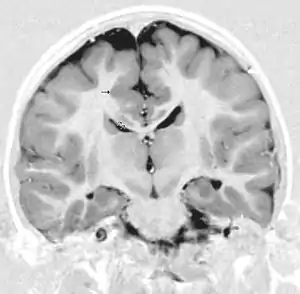

Polymicrogyria can lead to similar conditions that are linked to ulegyria such as mental retardation, cerebral palsy, and epilepsy. It has been observed that patients with polymicrogyria are not receptive to epilepsy surgery. However, responses of patients with ulegyria to similar surgeries are still not fully known, which makes distinction of these two disorders significant. In vivo neuroimaging techniques, namely MRI, have been instrumental in making this distinction. An MRI image of ulegyria is identified by mushroom shaped gyri, deformities in white matter, and localization mainly in the posterior cerebral region.[1] Polymicrogyria is typically recognized by a scalloped appearance at the bordering region between grey and white matter.[18] Although these distinctions have been made with many patients, there is still some difficulty in defining distinct boundaries between these two similar conditions.[7]

Primarily, the main method of detecting ulegyria is through the use of MRI screening for epilepsy. Normally an MRI of an ulegyria affected region will reveal groups of deteriorated neurons with gliosis present. In addition, unaffected gyri are also present in especially bilateral watershed regions indicating delayed effects of perinatal hypoxic damage.[4] However, there are three main criteria for diagnosing ulegyria using MRI in addition to the features mentioned above:[4]

1.The presence of a poorly demarcated lesion

2. Atrophy and thinning of the cortex resulting in the characteristic “mushroom” like shape of ulegyria.

3. Presence of white matter signal abnormalities as a result of FLAIR signaling (fluid attenuated inversion recovery).

Another sign of ulegyria that is visible on an MRI scan is the presence of a widened subarachnoid space, signifying cortex atrophy. FLAIR signaling can help visualize the depths of the parietal-occipital sulci, which also allows ulegyria-affected gyri to be identified.[6] Though there is still confusion in differentiating ulegyria and polymicrogyria in patients, MRI allows for the proper identification in the majority of the cases. In addition, most of the current research regarding ulegyria is focused on improving this identification. Furthermore, MRI can diagnose whether ulegyria presence is unilateral or bilateral.[1] Electroencephalography, EEG, can also be used to screen for ulegyria, though MRI is still preferred. This is mainly done for epilepsy patients as abnormalities in EEG recordings indicate the presence of ulegyria in the area of the brain being tested.[7] For example, when EEG tests in epileptic patients show deviations in the frontal and central-parietal regions, ulegyria can be considered to be present in that area.[7]